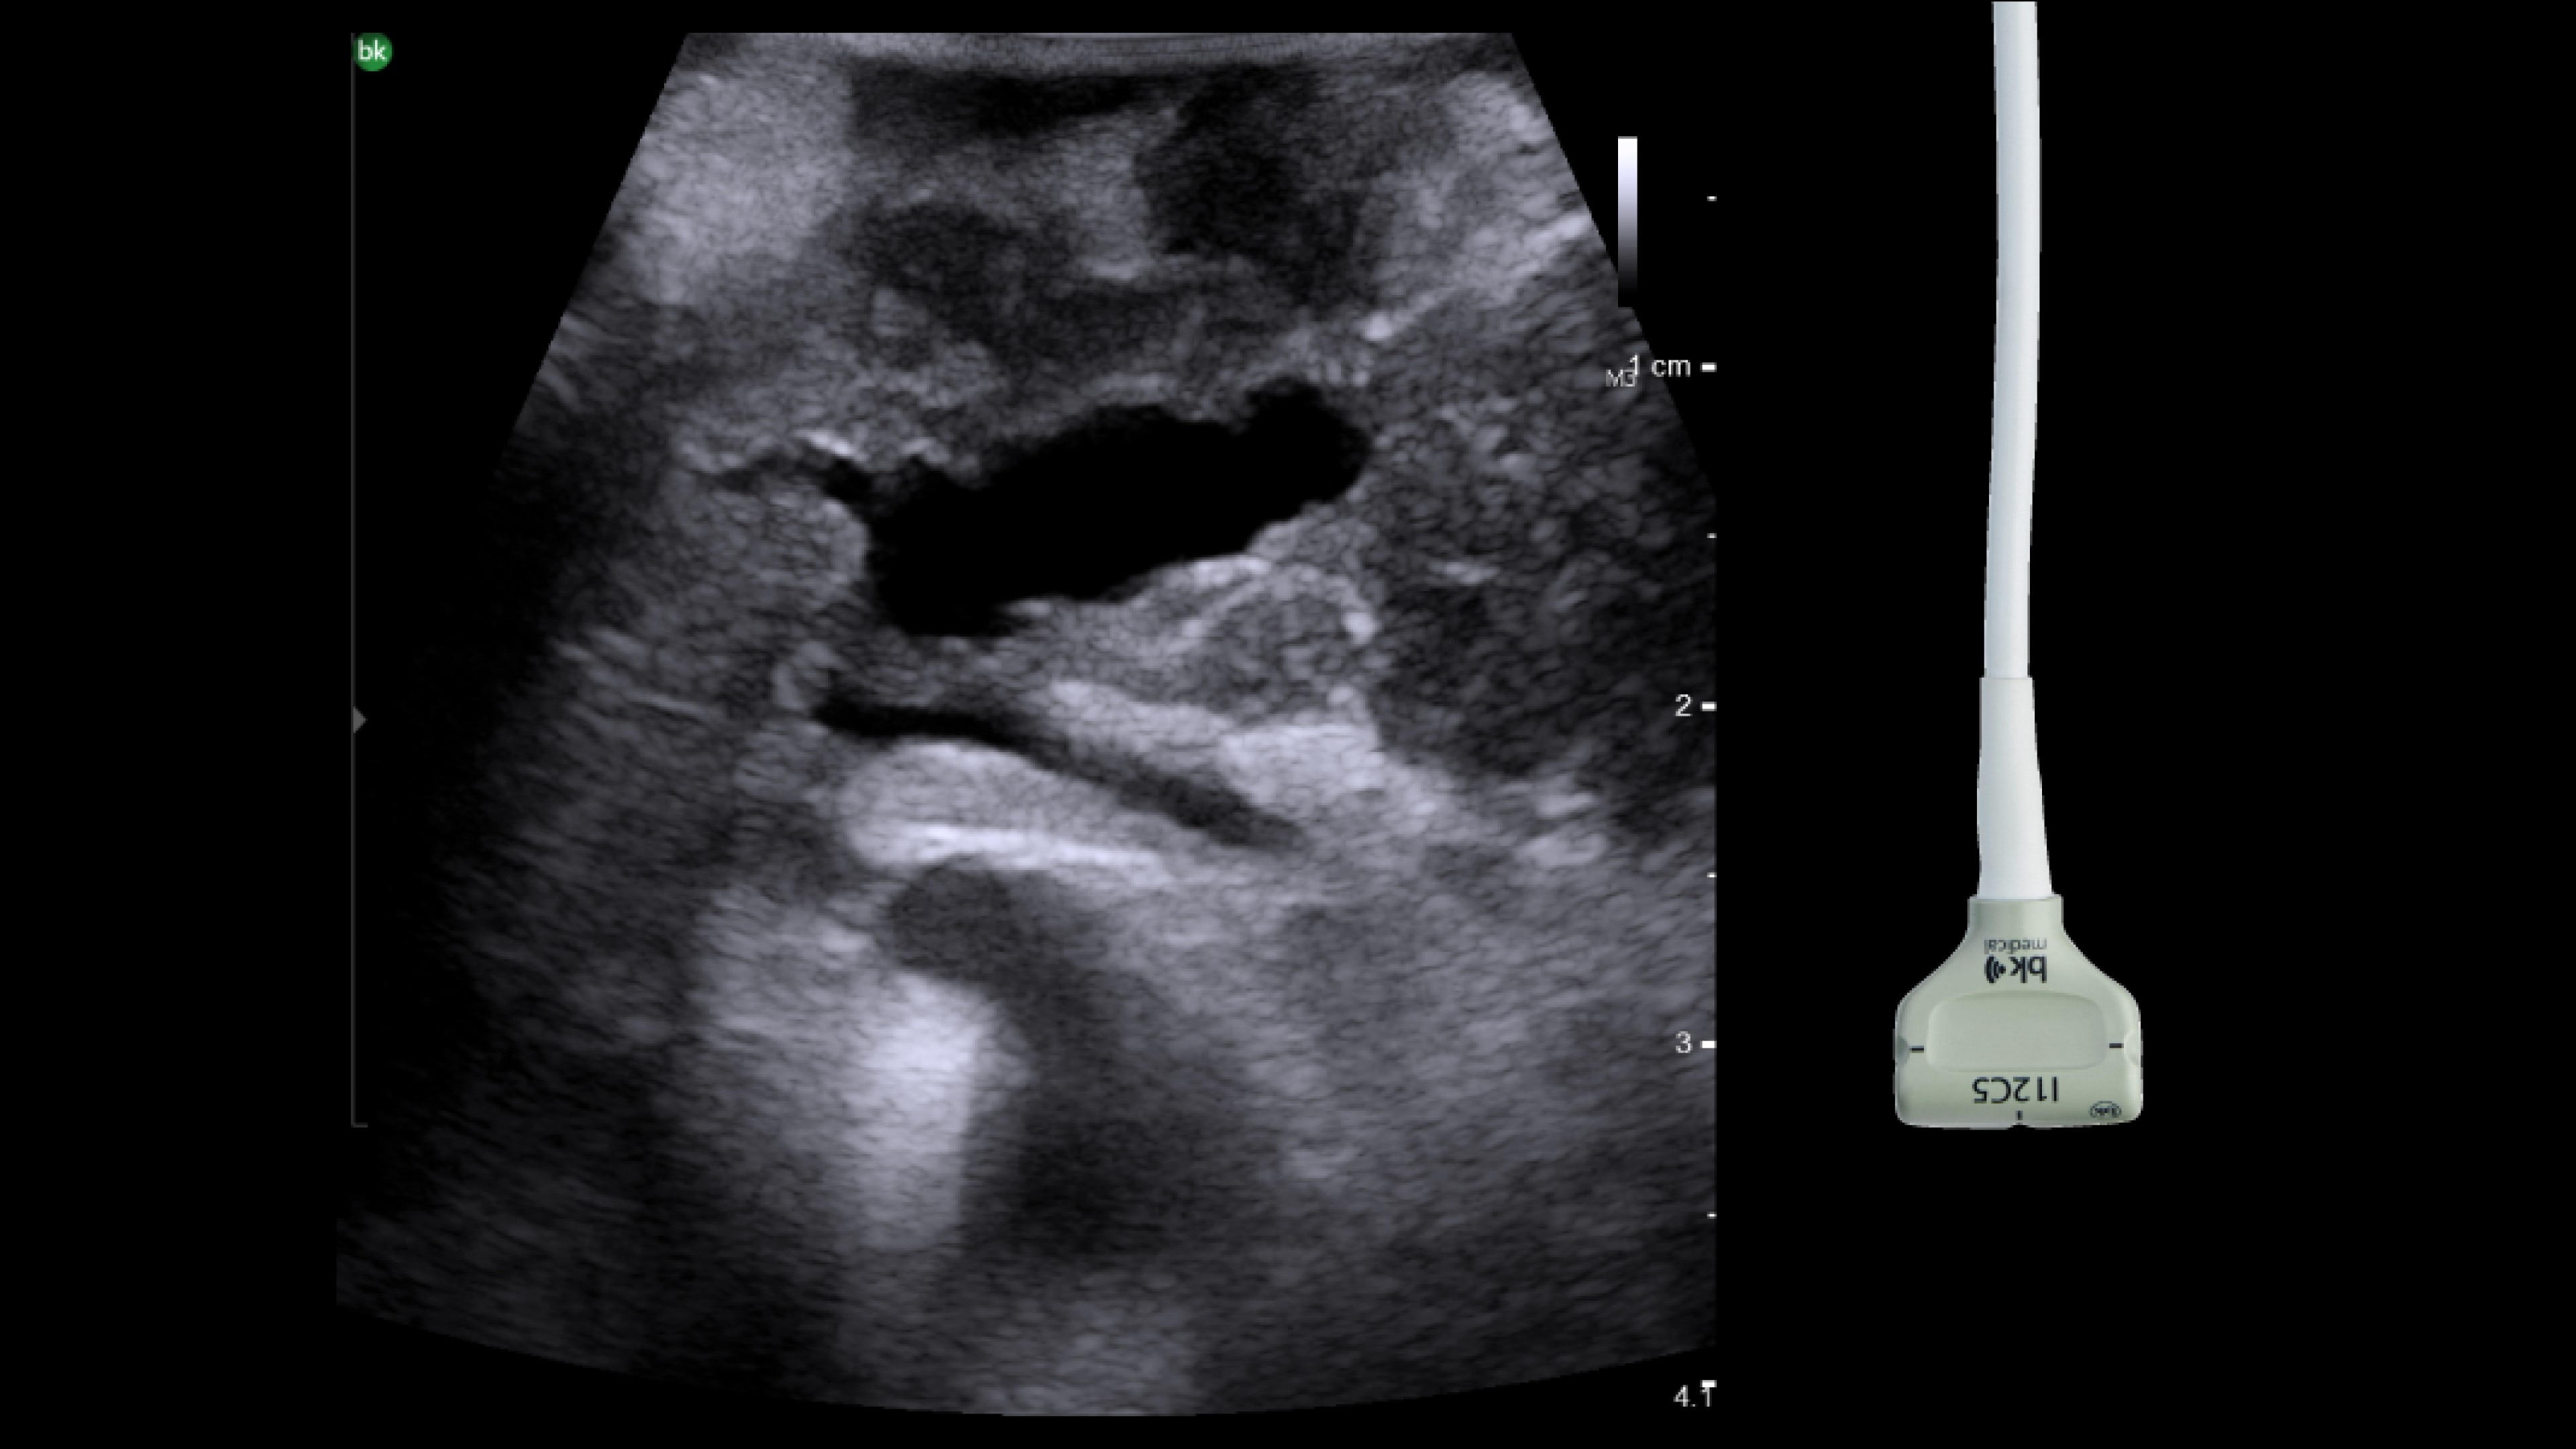

Active imaging supports liver and pancreas ablation procedures by helping you visualize lesions and blood vessels, identify healthy tissue vs. tumor, and guide and view needle placements.

Use intraoperative ultrasound to:

• Enable visualization of disease staging at the time of surgery with excellent image quality.

• Guide and view needle placements in real-time.

• Verify your planned results by assessing pre- and post-ablation images together.

Advanced Laparoscopic Transducer I13C3f*

• Plan and target tumor biopsies and ablations with patented laser technology.

• Achieve preferred insertion angle on up to two needles with proprietary channel design.